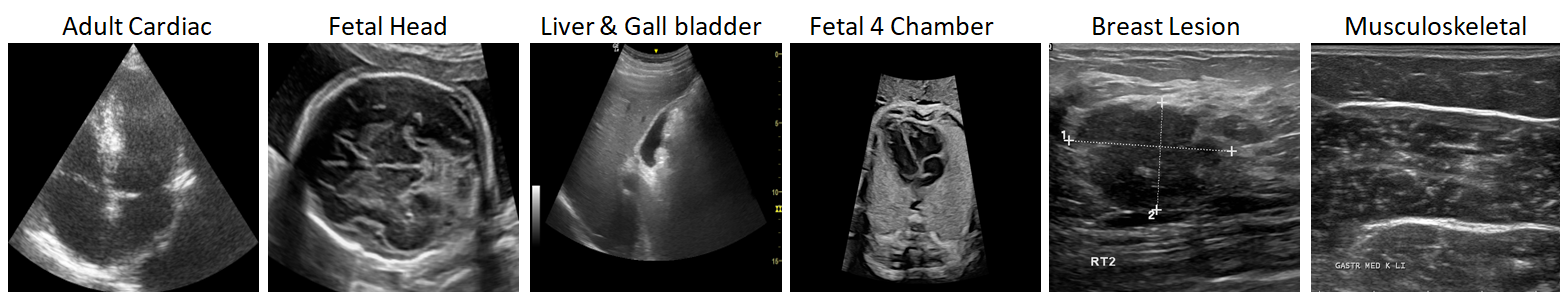

3 Training Data-sets

Ultrasound imaging poses challenges to any AI model development, specifically for foundation models due to poor SNR and CNR compared to other imaging modalities. Moreover, the concept of “objectness” do not translate well from natural images to ultrasound. As shown on few exemplar images in Fig. 3, the object boundaries are not often well defined, texture is highly varying and overall image quality has high inter-operator variability. To build generalized foundation models, training data-set has to be curated carefully to ensure sufficient diversity. We primarily utilized data from a wide variety of commercially available devices for training. Our training data-set (Table. 1) includes almost 200k images with 1) varying echogenicity: Hyper-echogenic structures like fetal cranium, hypo-echogenic regions, anechoic and fluid filled objects like fetal cardiac, 2) varying interfaces: objects with soft tissue boundaries like kidney, bone-tissue interface in fetal thorax 3) varying texture: homogenous texture like liver, thyroid, and heterogeneous texture in uterus. 4) varying image quality: 2-D( convex/ sector/ linear) probes, 3-D mechanical probes and electronic 4-D probes. We demonstrate the value of curating such diverse data in results section.